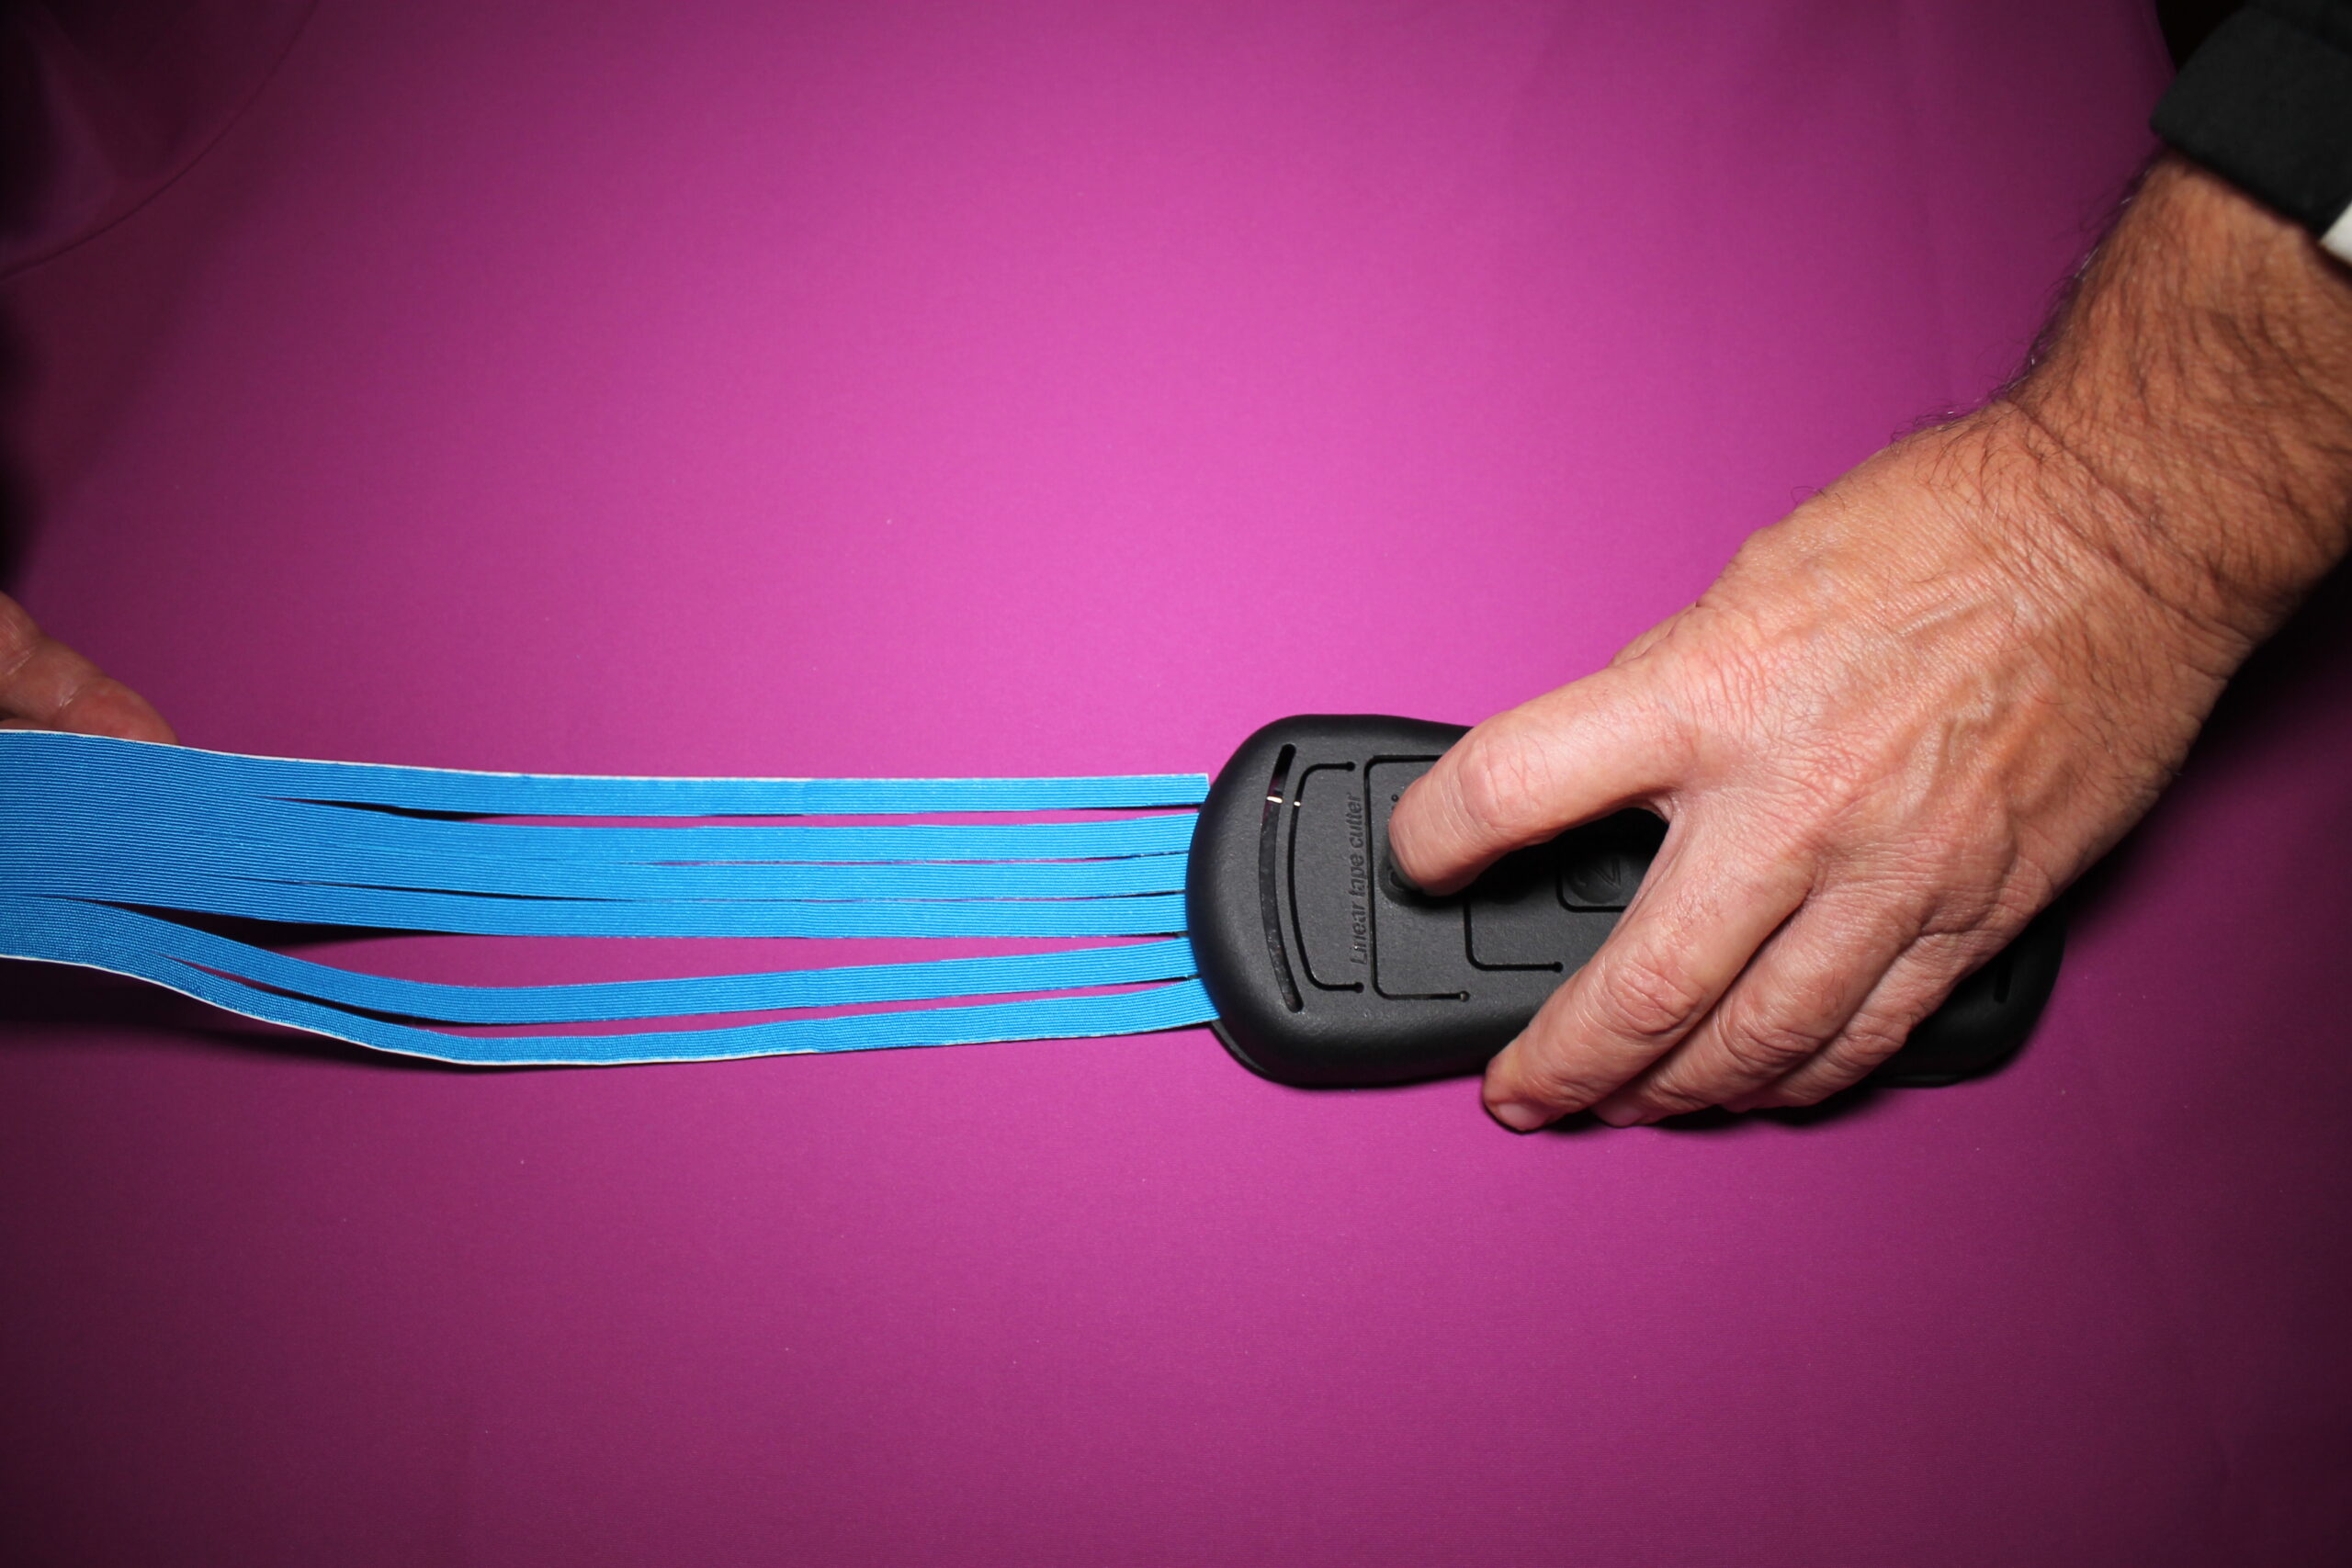

- Taping kinesiologico drenante della coscia sinistra